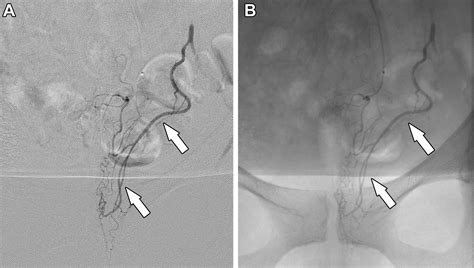

Hemorrhoid Artery Embolization is a cutting-edge, image-guided procedure performed by interventional radiologists. Unlike traditional surgery, which physically removes the hemorrhoidal tissue, HAE works by targeting the blood supply that feeds the hemorrhoids. By reducing the arterial blood flow to the hemorrhoidal plexus, the procedure causes the hemorrhoids to shrink over time, effectively alleviating symptoms like bleeding, pain, and protrusion.

Because it is a minimally invasive technique, it does not require general anesthesia or incisions in the sensitive anal region. Instead, a tiny catheter is guided through a blood vessel in the wrist or groin to the specific arteries supplying the hemorrhoids. Small particles are then injected to block these vessels, successfully reducing the pressure and engorgement of the hemorrhoidal tissues.

2. Guidance: Using real-time X-ray imaging (fluoroscopy), the radiologist navigates a microcatheter through the vascular system.

3. Embolization: Once the specific hemorrhoidal arteries are identified, specialized embolic agents are injected to reduce the blood supply.